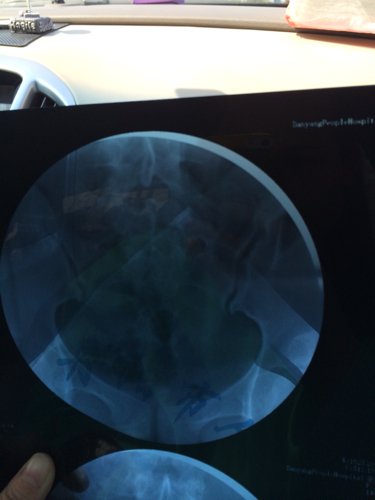

您好,医生。昨天我去做了一个子宫输卵管造影,结果检查所见子宫形态无明显异常。双侧输卵管伞部显影,双侧输卵管呈迂曲柔软的条状影。24小时后摄片示,造影剂在盆腔内积聚,弥散不良。检查结论双侧输卵管伞部碘油积聚,弥散不良,提示双侧输卵管伞部梗阻。请问医生我该怎么治疗,还有没有机会会人工受孕怀个健康宝宝呢?